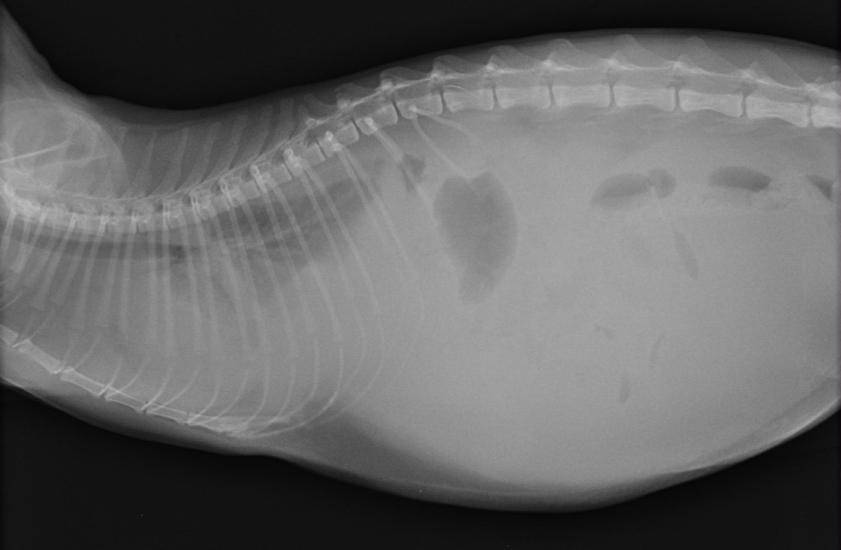

Лечебные методики, медикаментозную терапию назначит ветеринарный специалист после проведения комплексного осмотра четырехпалого пациента. Ветврач учитывает общие симптомы, данные анамнеза. Проводят рентгенографию, УЗИ брюшины. В обязательном порядке берут для лабораторных, микроскопических исследований транссудат из брюшины (пункцию). При исследованиях анализа мочи учитывают цвет, консистенцию, концентрацию белка.

Снимок узи брюшины, диагноз – асцит